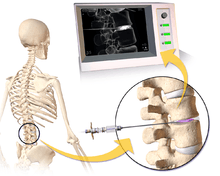

Lumbar provocative discography (also referred to as "discography" or discogram) is an invasive diagnostic procedure for evaluation for intervertebral disc pathology. It is usually reserved for persons with persistent, severe low back pain (LBP) who have abnormal spaces between vertebrae on magnetic resonance imaging (MRI), where other diagnostic tests have failed to reveal clear confirmation of a suspected disc as the source of pain, and surgical intervention is being considered.

Needles are inserted through the back into the disc near the suspect area, guided by fluoroscopic imaging. Fluid is then injected to pressurize the disc, and any pain responses are recorded.

A contrast agent is introduced, and after the procedure a CT scan identifies leakage from the discs to identify any spinal disc herniation.